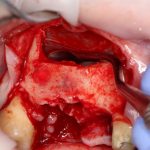

В ходе проведения операции синуслифтинга, у нас образовалась небольшая перфорация шнайдеровой мембраны:

Мы начинаем с того, что выводим ее в центр апертуры, попутно мобилизуем края. В результате, она несколько уменьшилась в размерах: